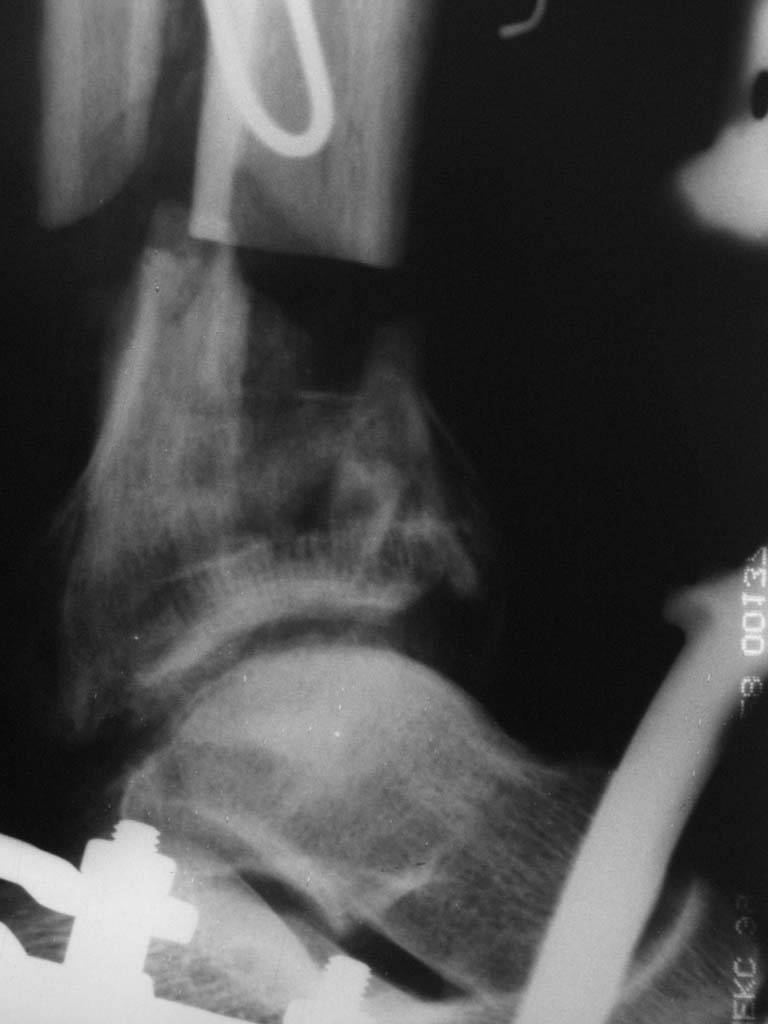

Больному выполнена резекция малоберцовой кости, ВХО раны, сближение отломков. Резекция м\б через отдельный разрез. После ВХО компрессия в аппарате, края раны сближены наводящими швами (без натяжения).

В случае гладкого заживления раны, при условии положительного решения вопроса с металлом, планируем перемонтаж аппарата Илизарова, дополнительную резекцию дистального отломка, выведение полокости голеностопного сустава в правильное положение (см. боковую Р-грамму), одномоментно остеотомия большеберцовой кости. После восстановления длинны голени, по всей видимости, артродез голеностопного сустава.

Рентгенограммы прилагаются. Фото местного статуса выложу в ближайшее время.